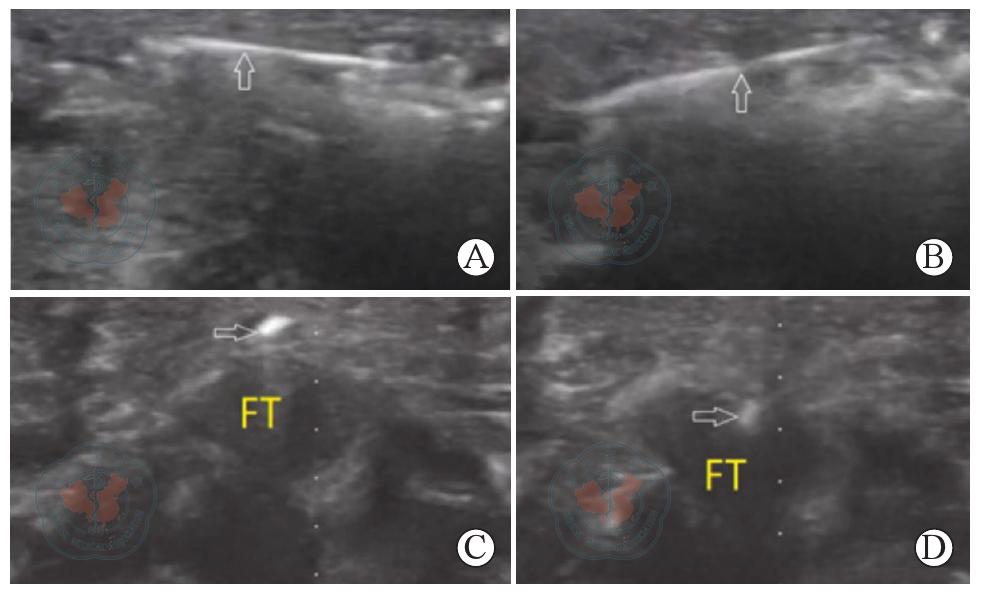

图6 套管针验证右手第5手指近端掌指关节腱鞘松解效果超声影像。图A~B为掌指关节纵切面,见针(白色箭头)在肌腱上方自由上下摆动;图C~D为掌指关节横切面见针(白色箭头)在肌腱上方自由上下摆动,证实腱鞘的松解完全注:FT-屈肌腱

Figure 6 Confirmation of tendon sheath release in the right fifth finger metacarpophalangeal joint using the cannula with ultrasound images. A~B is longitudinal ultrasound view, showing the cannula (white arrows) moving freely in the tendon sheath; C~D is transverse ultrasound view, showing the cannula (white arrows) moving freely in the tendon sheath, confirming complete release of the tendon sheathNote: FT-flexor tendon